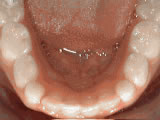

Spacing of teeth

Before

AfterPatient was bothered by the spaces between his teeth. Braces closed the spaces and gave him an ideal bite in 24 months. Special glued-in retainers help keep the spaces closed.